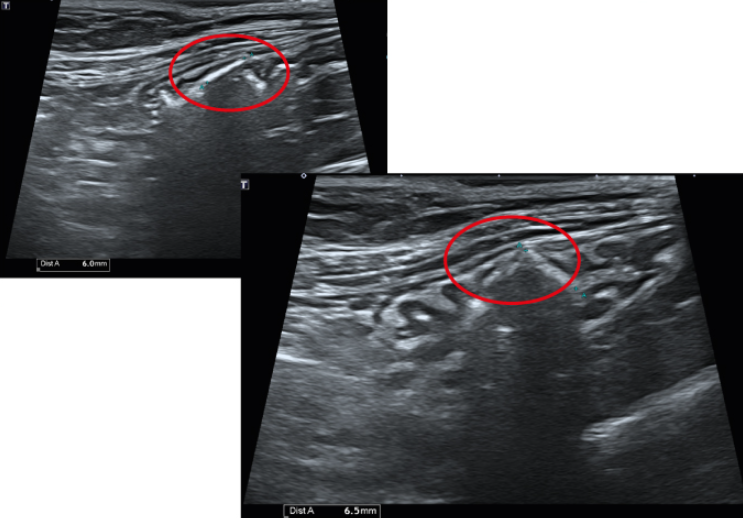

복부 초음파 검사상 위 내 shadowing을 일으키는 판상의 물질이 확인되었는데 아이가 뜯어먹은 고무 매트로 추정됩니다.

.png)